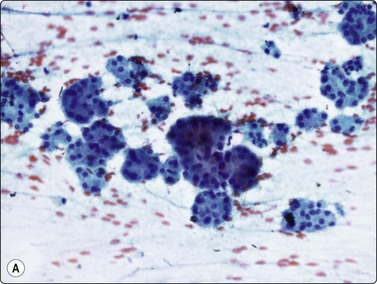

image image

Fig. 11.10 Adenocarcinoma (pancreas)

Well-differentiated adenocarcinoma; relatively mild nuclear atypia, but nuclear crowding and some dissociation, and in B a tendency to microacinar arrangement (A, MGG, HP; B, H&E, HP).

Almost all adenocarcinomas arising in the pancreas are of ductal origin, without unique features permitting absolute distinction from carcinomas arising in the biliary tree. The characteristic FNB pattern is of crowded ‘drunken’ monolayered sheets, with moderately tall columnar palisading cells at luminal edges. Smaller aggregates commonly show rounded glandular structures with feathered edges, or three-dimensionality. Cytoplasmic borders may be very well demarcated in better-differentiated forms; in other cases, the monolayer sheets appear syncytial. The diagnosis of malignancy ultimately depends on nuclear features, which range from very subtle alterations to overly malignant criteria with decreasing differentiation (Figs 11.9-11.11). In an assessment of individual criteria by regression analysis, Cohen and colleagues extracted as most important: anisocytosis (4 : 1), nuclear enlargement and molding, with combined sensitivity of 98% using all three criteria to distinguish malignant from benign.70 In a similar study, Robins, Katz and Evans ascribed major status to nuclear crowding, contour and chromatin irregularity, minor status to single cells, mitoses and enlarged nuclei,33 requiring two major, or one major and two minor criteria for the definitive diagnosis of malignancy. Focusing specifically on the most challenging area, the recognition of well-differentiated carcinoma, Lin and Staerkel listed the following features: nuclear enlargement > 2 rbc (99%), anisonucleosis 4 : 1 (97%), nuclear membrane irregularity (97%), and crowding/overlapping/three-dimensionality (92%).73